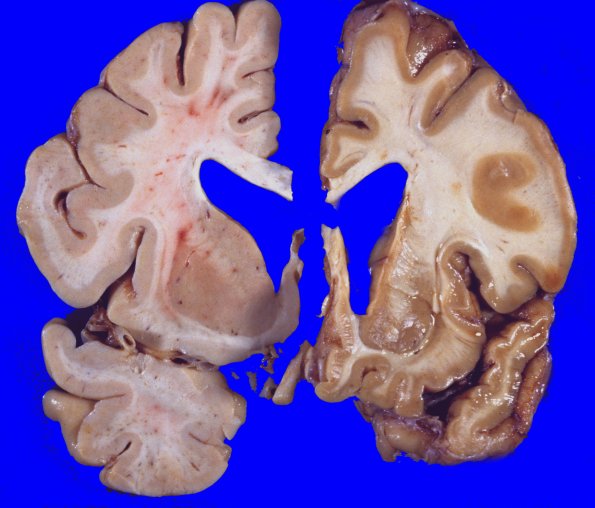

Comparison of coronally sectioned half-brains control (left) and HD brain (right) sections through one cerebral hemisphere show cortical atrophy involving chiefly the frontal and parietal lobes. The deep gray nuclei are remarkable for the shrinkage and slight discoloration of the head of the caudate nucleus. Rather than bulging in a convex appearance, it has become flattened against the lateral aspect of the lateral ventricle. The ventricle itself is significantly blunted and dilated.